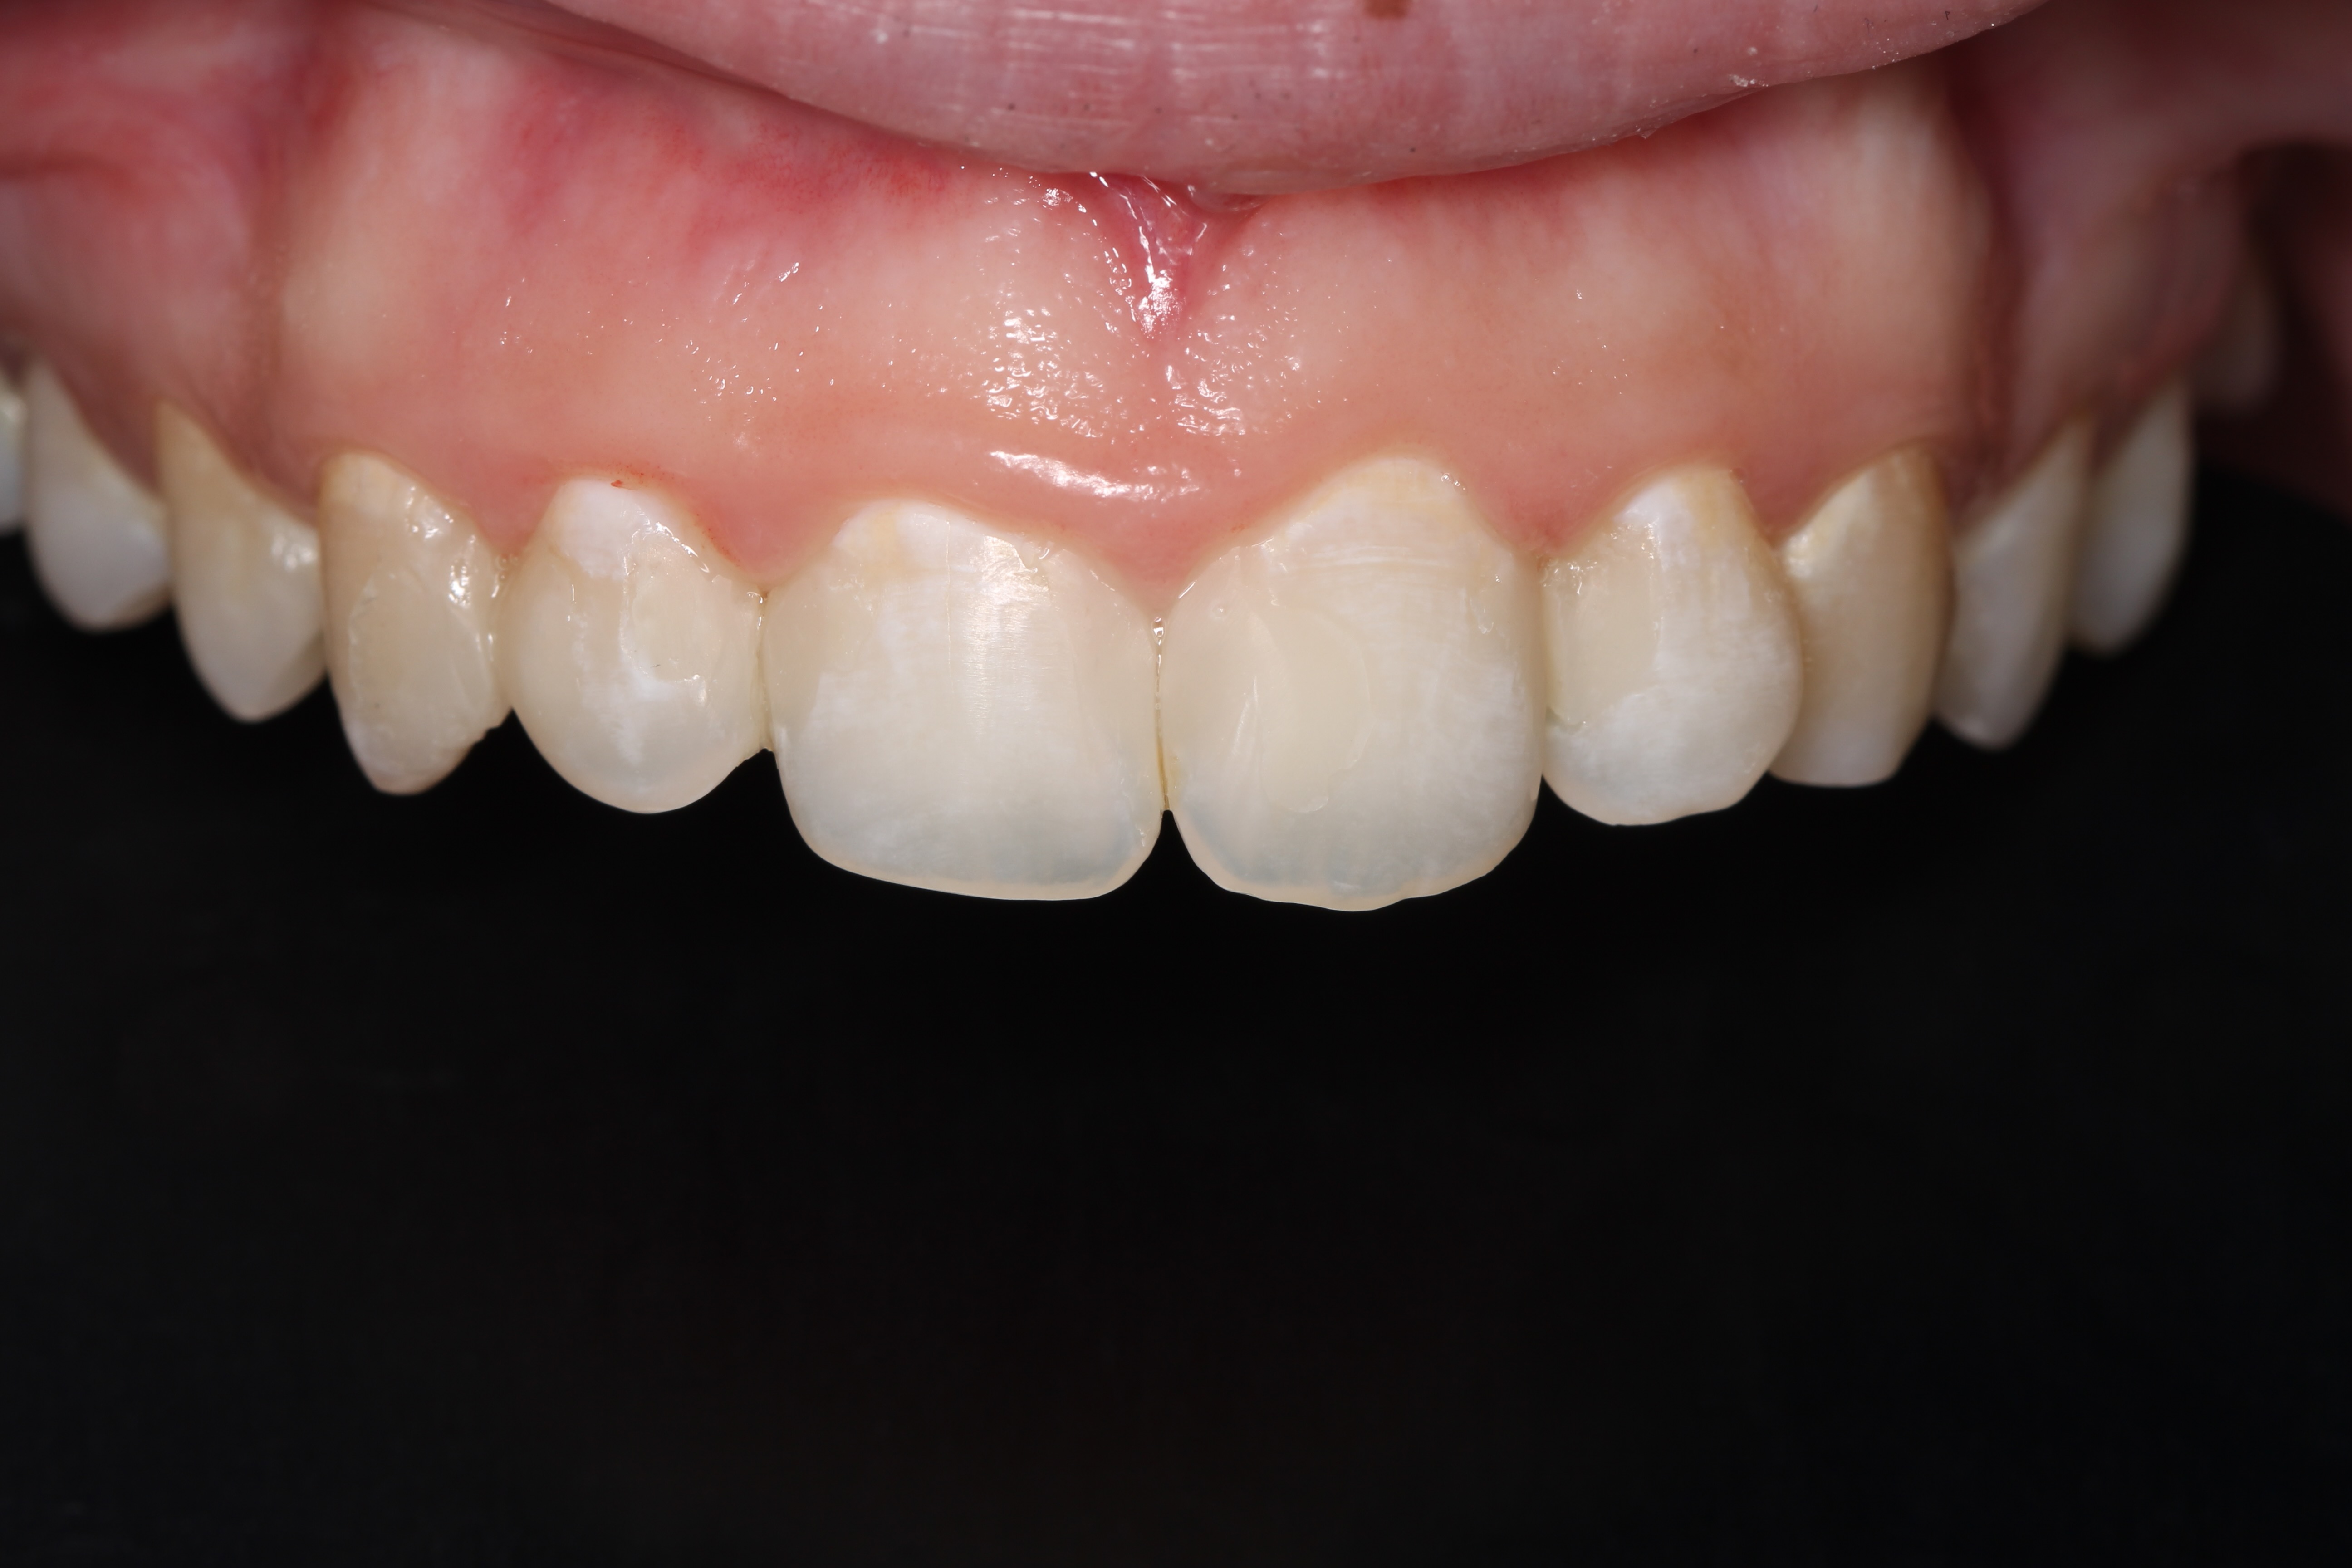

Anterior ceramic crowns and smile design by Mr Stefano Del Monte

From this course, I learned the whole workflow involving designing crowns for an aesthetic case. I learned how to work alongside the lab to create digital smile wax-ups, how to manage patient expectations and prepare teeth quickly and effectively for anterior crowns and veneers.play your timeline of professional development